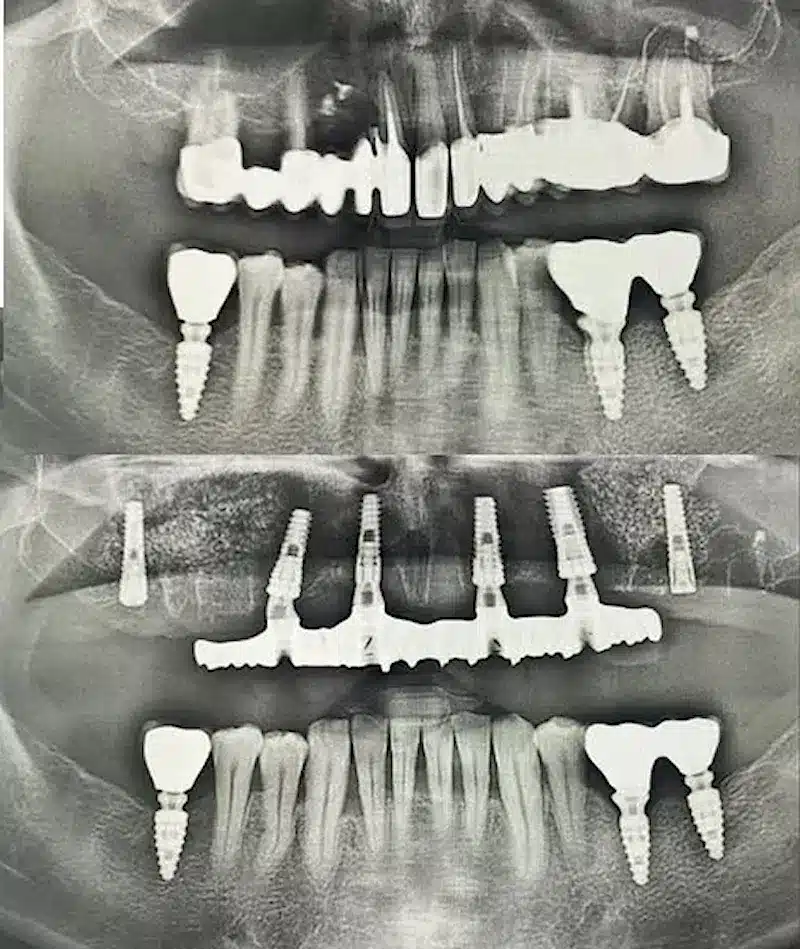

Dr. Seden Aksu is a specialist in modern implantology and surgical dentistry with extensive experience in the management of complex clinical cases. In her practice, she applies comprehensive surgical planning, minimally invasive techniques, and advanced regenerative technologies aimed at restoring both the function of the dentoalveolar system and the aesthetics of the smile. Dr. Aksu has significant experience in performing implant procedures, bone augmentation, and periodontal surgery, including the treatment of patients with severe bone loss. The primary goal of her work is to achieve stable, long-term outcomes in implant rehabilitation and the restoration of oral tissue health.